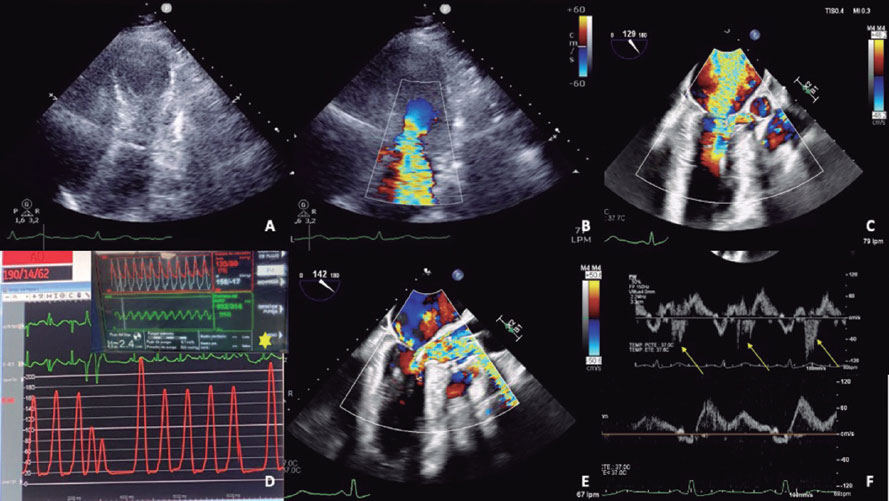

A 77-year-old woman was admitted for non–ST-segment elevation acute coronary syndrome, Killip class III. The emergency cardiac catheterization showed a chronic non-occlusive lesion in the mid left anterior descending coronary artery, which was treated. The clinical course, after recovery of left ventricular ejection fraction, suggested the presence of tako-tsubo syndrome (figure 1A,B).

Despite the administration of fluid therapy and esmolol to reduce dynamic left ventricular outflow tract obstruction (DLVOTO), the patient progressed to SCAI-D cardiogenic shock and required vasopressors, intubation, and intra-aortic balloon pump implantation at a 1:3 ratio to avoid exacerbating DLVOTO. Given the ongoing deterioration, escalation to Impella CP (Abiomed, Inc., United States) as a bridge to recovery was decided. Organic mitral valve disease was ruled out. Since the mitral regurgitation was due to systolic anterior motion (figure 1C; video S1), an emergency septal ablation was planned.

Implantation of the Impella-CP device (figure 1D, asterisk), with flow adjusted to 2.4 L/min (P4) to prevent suction, resulted in immediate hemodynamic and respiratory improvement, as well as a reduction in mitral regurgitation (figure 1E,F; arrows indicate the systolic S wave). A second septal branch (SB) showed extrinsic compression and was selected after confirmation of septal perfusion (figure 2A; arrow indicates second SB; asterisk: first SB). Two coils were deployed (figure 2B) due to potential reversibility, resulting in immediate flow reduction and DLVOTO improvement.